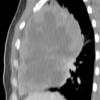

Lymphoma CT Sag

Date: 04/25/2009

Views: 2936